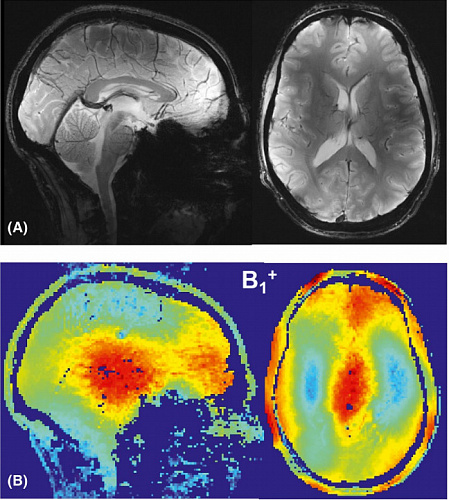

Найден способ увеличить разрешение томографических снимков, изменив геометрию диполей в магнитной катушке

Физики из ИТМО вместе с коллегами усовершенствовали геометрию диполей — устройств, создающих магнитн...